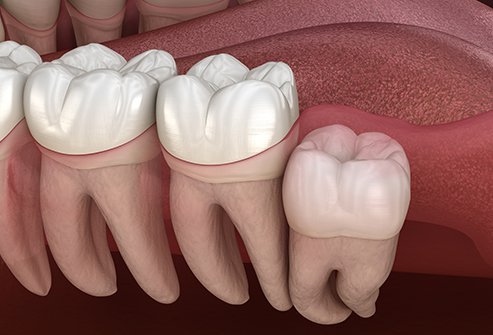

They usually erupt at the age of 18-21. Because of the refine food people often take, our jaw could not accommodate 32 teeth anymore causing the last tooth to erupt to be impacted. This would cause incomplete eruption, space in between teeth, tooth decay, pericoronitis, roots’ resorption of adjacent teeth, infection, pain and sometimes cellulitis.

When this tooth is erupting you will experience pain, discomfort and swelling. These problems could be controlled by medicines. Usually wisdom teeth are fully formed when they erupt and the jaw is also fully grown at the same time, thus, there would not be enough space for them to erupt fully. They could be slanted, angulated, partially or fully embedded in bone and exposing only a small portion in the oral cavity. These made them difficult to notice. Because of these incorrect positions, usually they are non functional. Because of certain angulations, there may be food impaction causing tooth decay, foul breaths and gum diseases. These problems could also spread to the adjacent second molar if left untreated.

Extraction is usually advisable at the age of 18-25 if the wisdom tooth is symptomatic. Most of the time the tooth is still not fully formed and the jaw bones are not so compact, making the extraction less traumatic and simple.